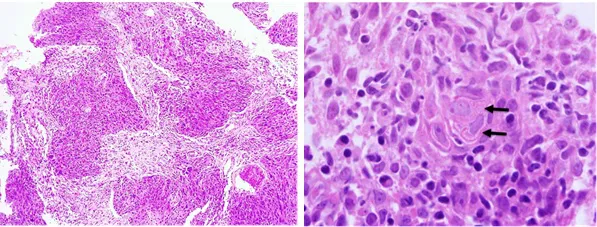

It is characterized by malignant squamous epithelial cell proliferation with evidence of keratinization and invasive growth pattern. Keratin pearl formation is common. Invasion into the stromal tissue is often accompanied by a desmoplastic changes, accompanied by chronic inflammatory cells (Fig. 2). In general, it is graded into well-, moderately-, and poorly differentiated. Well-differentiated SCC exhibits mild nuclear atypia with keratin pearls, whereas poorly differentiated SCC display highly pleomorphic and hyperchromatic cells, with numerous typical and atypical mitoses, minimal keratinization, and sometimes necrosis. In this case, the presence of intercellular bridges is an important diagnostic clue for squamous differentiation or origin. Most SCCs are moderately-differentiated, which exhibit features in between well-differentiated and poorly differentiated carcinoma. HNSCCs express most epithelial markers such as cytokeratin. However, in well-differentiated SCC, diagnosis can be made by H&E without additional stains. In poorly differentiated tumors, immunohistochemistry may play a role. HNSCCs are immunopositive for pan cytokeratin. CK5/CK6, p63 and p40 are excellent markers for squamous differentiation [3, 4].

Keratinizing squamous cell carcinoma (KSCC). Left (H&E 100X): Infiltrating tumours are seen arranged in large irregular sheets surrounded by desmoplastic stroma. Right (H&E 400X): The intercellular bridges (arrow) is present.